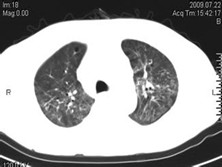

非特异性间质肺炎(非特异性间质肺炎)

非特异性间质性肺炎(NSIP)是特发性肺间质性疾病(ⅡP)的一种类型。过去归纳在特发性肺间质纤维化中,因其临床、病理、影像学、肺功能等改变,尤其对糖皮质激素的治疗反应和预后与IPF都有显著的不同,故近年将其从IPF中分离出来,作为一种独立的特发性肺间质疾病。因其临床症状和病理特点相对缺乏特异性,临床多被诊断为IPF,实... [详情]